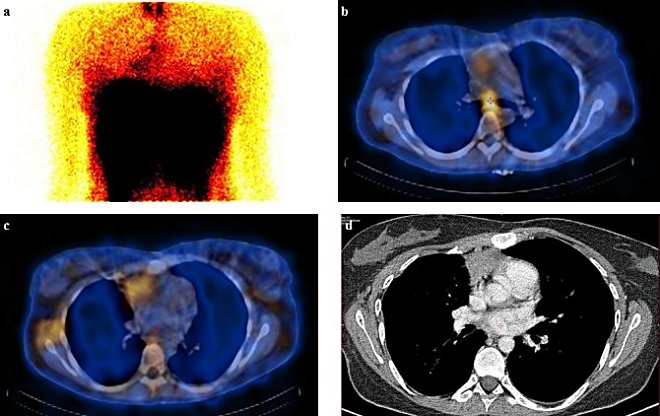

Při víceoborovém semináři dohodnuto v polovině roku 2013 doplnění vyšetření PET, a to s fluorodeoxyglukozou (FDG) a následně s preparátem F-DOPA

(FD) - při lepším prostorovém rozlišení PET jsme doufali v přesnější identifikaci morfologického korelátu nálezu na Octreoscanu, který by umožnil radikální lokální terapii. FDG PET z 5.6.2013 však zachytil pouze aktivaci hnědého tuku, bez patologického hypermetabolického ložiskového nálezu maligního charakteru

(obr. 8a, 8c). Stejně tak při vyšetření pomocí FD ze 27.6.2013 jsme neidentifikovali fokální zvýšení akumulace radiofarmaka

(obr. 8b, 8d), tentokrát však při cíleném posouzení oblasti při karině nacházíme v CT obraze ventrálně od větvení trachey denzní tkáň, která by mohla odpovídat LU a mohla by být hledaným korelátem  změn pozorovaných na Octreoscanu

/ Obr. 8:

PET vyšetření: 8a,c FDG z 5.6.2013 (8a MIP projekce, 8c fúzovaný PET/CT řez v úrovni mediastina), 8b,d F-DOPA z 27.6.2013 (8a MIP projekce,

8c fúzovaný PET/CT řez v úrovni mediastina), obě vyšetření bez patologického ložiskového nálezu (při vyšetření FDG patrná aktivace hnědého tuku- fyziologická varianta).